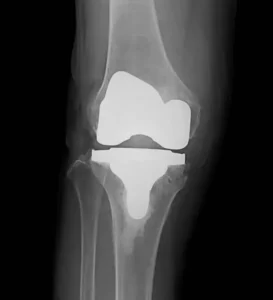

人工ひざ関節全置換術 TKA

- 手術の目的

関節全体の痛みを取り除き、歩行や階段昇降などの日常生活動作を改善

することを目的とします。

- 適応疾患

- 変形性ひざ関節症

- 関節リウマチ

- 外傷後の二次性変形ひざ関節症

- 手術の内容

コンピュータナビゲーションシステムを使用し、手術中にリアルタイムで骨切り角度やインプラント設置位置を確認。

- メリット

- 強い痛みの改善。

- 日常生活の動作が楽になる。

- 関節の安定性が向上し、歩行がスムーズに。